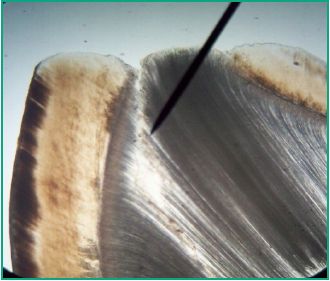

The histologic specimens obtained were classified according to the scale mentioned above, and analyzed using an optical microscope at different magnifications: 10x, 20x and 40x (Figs. 4-8).

Fig. 7. 20x microscope image of enamel and dentin in a tooth

with grade III wear

The histologic specimens obtained were classified according to the scale mentioned above, and analyzed using an optical microscope at different magnifications: 10x, 20x and 40x (Figs. 4-8).

Fig. 7. 20x microscope image of enamel and dentin in a tooth

with grade III wear

The enamel wear of teeth with Grade I wear was examined macroscopically on the occlusal/incisal surface, which showed microfractures that can be seen under white light. The areas of attrition appeared as polished and shiny surfaces when they only included enamel. The section of the enamel prisms of teeth with grade I wear was observed under the optical microscope at 20x magnification (Fig. 4). Dentin was translucent and yellowish, due to the deposit of peritubular dentin obliterating the dentinal tubules, all of which is consistent with sclerotic dentin (Fig. 5). In the cases where attrition only reached the enamel, the section of the adamantine prisms observed was consistent with tissue that does not respond to any stimuli. The presence of reactive or defensive dentin was observed. The microscopic examination of the teeth with grade II wear, according to the modified scale, showed discontinuities on the enamel on the areas closest to the outer tooth surface, and the peripheral areas of the dentin showed wear in small spots (Fig. 6). The teeth with grade III wear showed exposed dentin, and a central opaque yellow concavity surrounded by irregularly worn enamel which was visible to the naked eye. Sclerotic dentin was observed in the periphery, and dead or devitalized tract dentin was observed in the center of the teeth under the optical microscope at a 20x magnification (Fig. 7). At a higher magnification (40x), it can be seen that the dentinal tubules were empty, covered in germs and organic residue from the mouth (Fig. 8). They seemed dark due to the contamination with the wear technique material and the balm used to prepare the histologic specimen. Dead tract dentin was visible with 20x and 40x magnification due to the fact that the wear took place in a short period of time and there was no time for the odontoblasts to retract. However, some teeth showed both types of dentin.

The direct correlation between the amount of worn down dental tissue and the rate at which the tooth is worn down must be taken into account, as it is a sign of the fact that the maxillae are growing adequately and, therefore, that occlusion is evolving correctly. During the microscopic examination we found sclerotic or translucid dentin, which, according to some authors (4), is only produced in the presence of the odontoblast processes that secrete the matrix inside the lumen of the tubules (Fig. 7). The formation of sclerotic dentin is a defense mechanism for compensating the regional loss of surface dentin. Its quality and quantity are connected to the duration and intensity of the stimulus. Therefore, if it is formed quickly, the tubular pattern will be irregular and there can often be odontoblasts included. Exposure of the pulp and dentinal sensitivity are not common because loss of the tooth structure is slow, thus enabling the apposition of the secondary-reparative dentin (10). No variation was found in the direction of the dentinal tubules. The analysis of the dentin during non carious processes has shown that the variability in the irregular or atubular dentin is not related to the type of harmful stimulus or to the destructive process of teeth, although a mild change in its path has been detected.